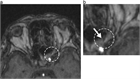

1. 治療法に関し、ステロイドの投与、外科的視神経減圧術ついてテキスト、画像を追加した。